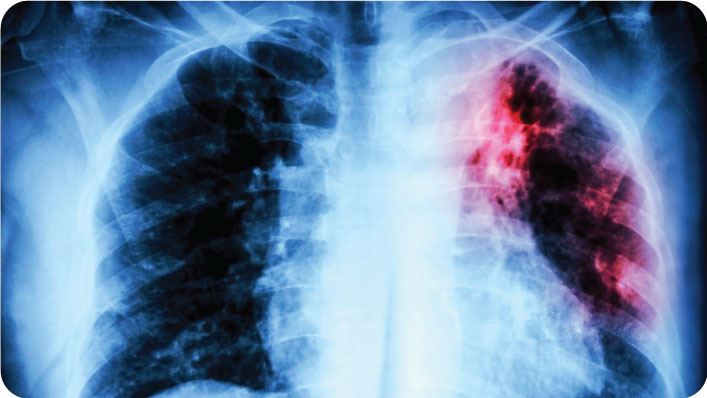

3) Tuberculosis (TB)

TB is the second leading cause of death from infectious disease globally, after COVID-19. In Tanzania, TB disproportionately affects people with HIV and those in crowded or poor conditions. Multi-drug resistant TB is an increasing threat.